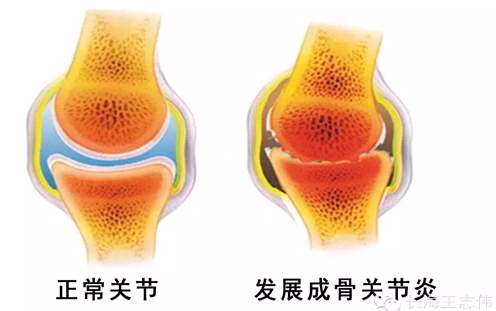

骨赘又称骨刺或骨唇。指骨关节周缘(尤其是关节软骨缘)出现反应性的局部骨质增生。常发生于骨关节劳损或退行性改变、外伤性骨关节炎等病变中。它可能引起局部疼痛,过大的骨赘可能影响关节活动,如赘生物脱落到关节腔内则成为关节鼠。

但从狭义的角度,骨赘、骨质增生是相同的意思。而这些都可以称作骨关节炎。

1、年龄:随着年龄增长,蛋白多糖下降,含水量下降,抗疲劳能力下降,关节软骨退变,骨质增生增加。